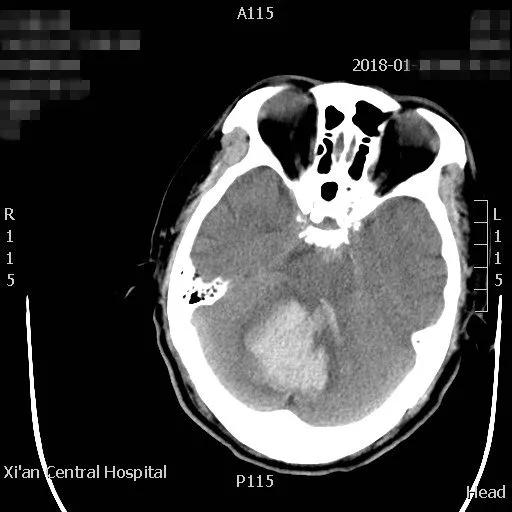

近日,一位六十岁的男性,在家中突发头痛、呕吐、左侧肢体瘫软无力摔倒在地,被家人急送市中心医院急诊科,急诊接诊后发现患者处于昏迷状态,遂急查颅脑CT并请神经外科会诊。CT结果显示患者小脑出血40毫升,即刻收住神经外科住院。

患者病情危重,出血点位于后颅窝靠近天幕,位置狭小、深在、靠近脑干、直视困难,应用普通手术操作困难,容易损伤脑干,血肿也不容易彻底清除。主管主任医师王占尧对该患者进行了详细的查体后,与治疗小组商议手术方案。为进一步减少小脑皮层损伤、降低颅脑创伤,王占尧主任医师决定对该患者使用内镜辅助清除血肿。